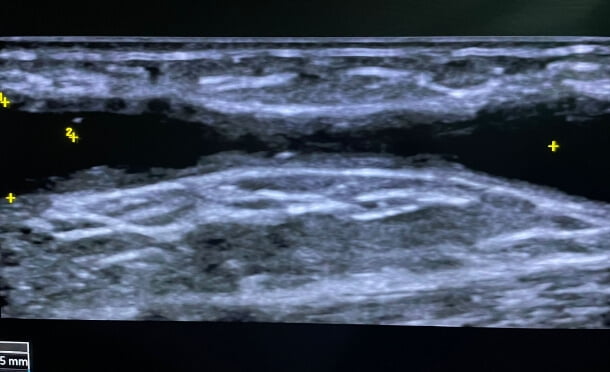

Ultrasound-Guided Thrombatherectomie:

A BYCROSS® Case Study